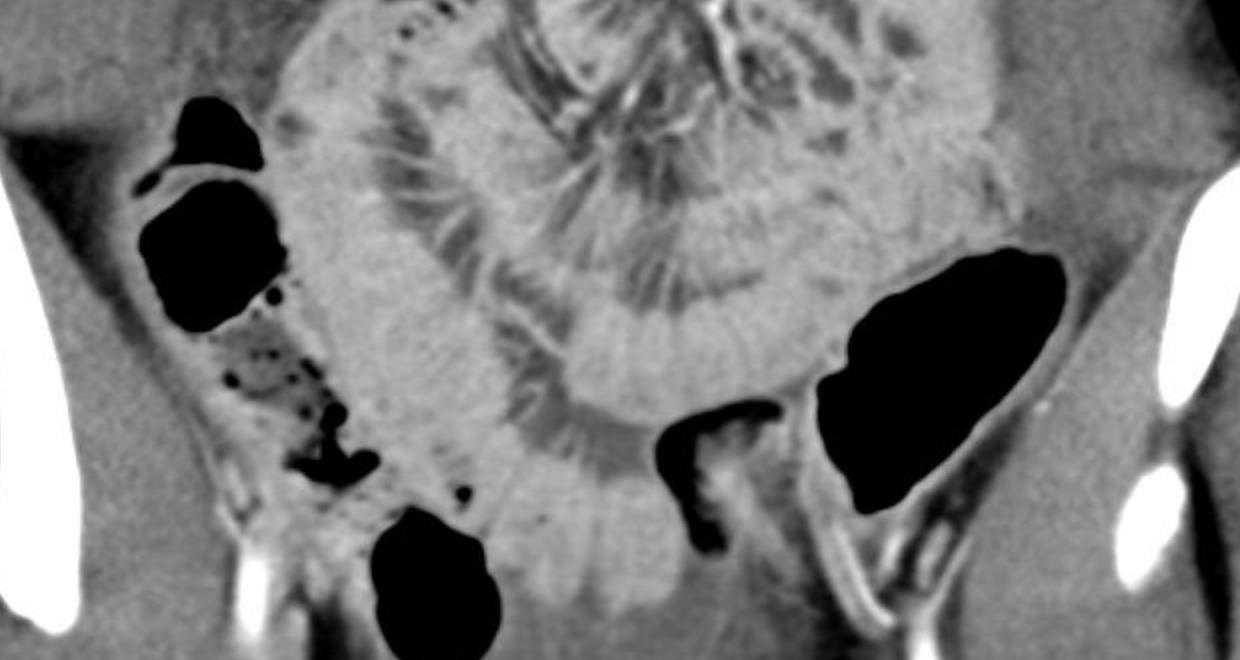

Abdominal abnormalities

Hollow viscera abnormalities

Bowel wall thickening

Bowel dilation

• Gastrointestinal (GI) symptoms (abdominal pain, diarrhoea and vomiting) are prevalent in MIS-C

• Abdominal pain in 62%

• Up to 90% any GI symptom

• Anumber of studies have described abdominal imaging findings including ascites, bowel wall thickening and mesenteric lymphadenopathy